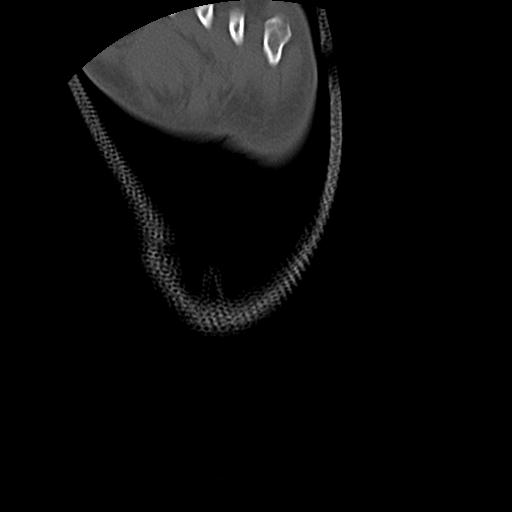

56476 8/28 4R 1/21 2R 左足関節 デジカメ写真 72歳女性 右足関節AS